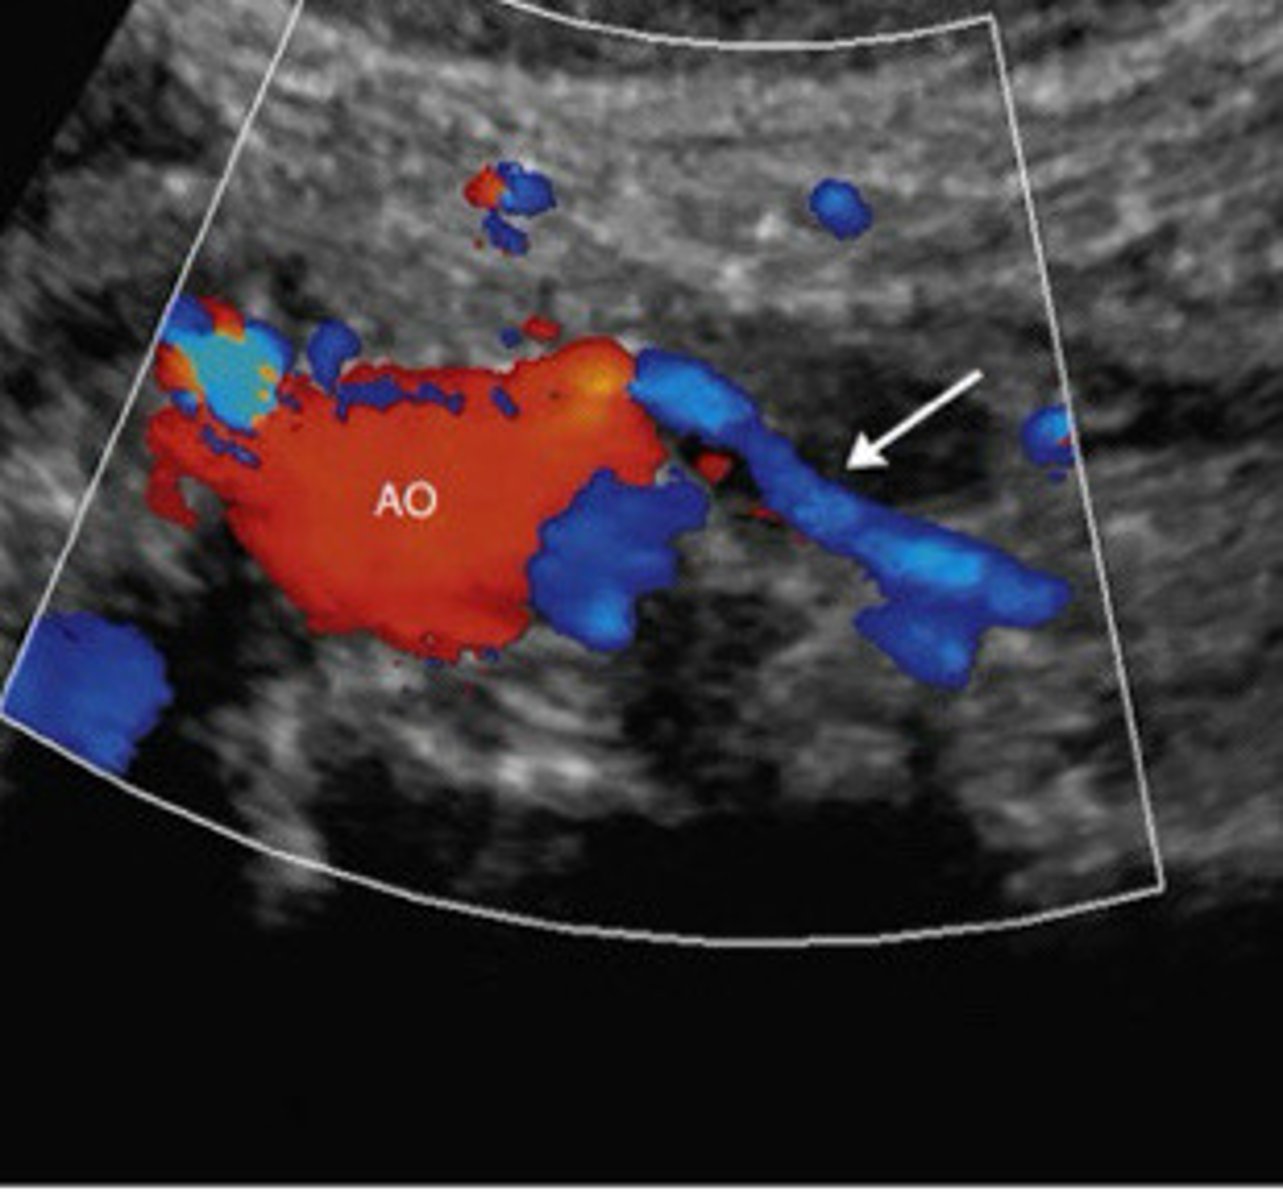

Around 1:00 in to the left

Describe the take off of the IMA off the aorta that is usually seen in transverse

Normal take off of the IMA

What does this image show